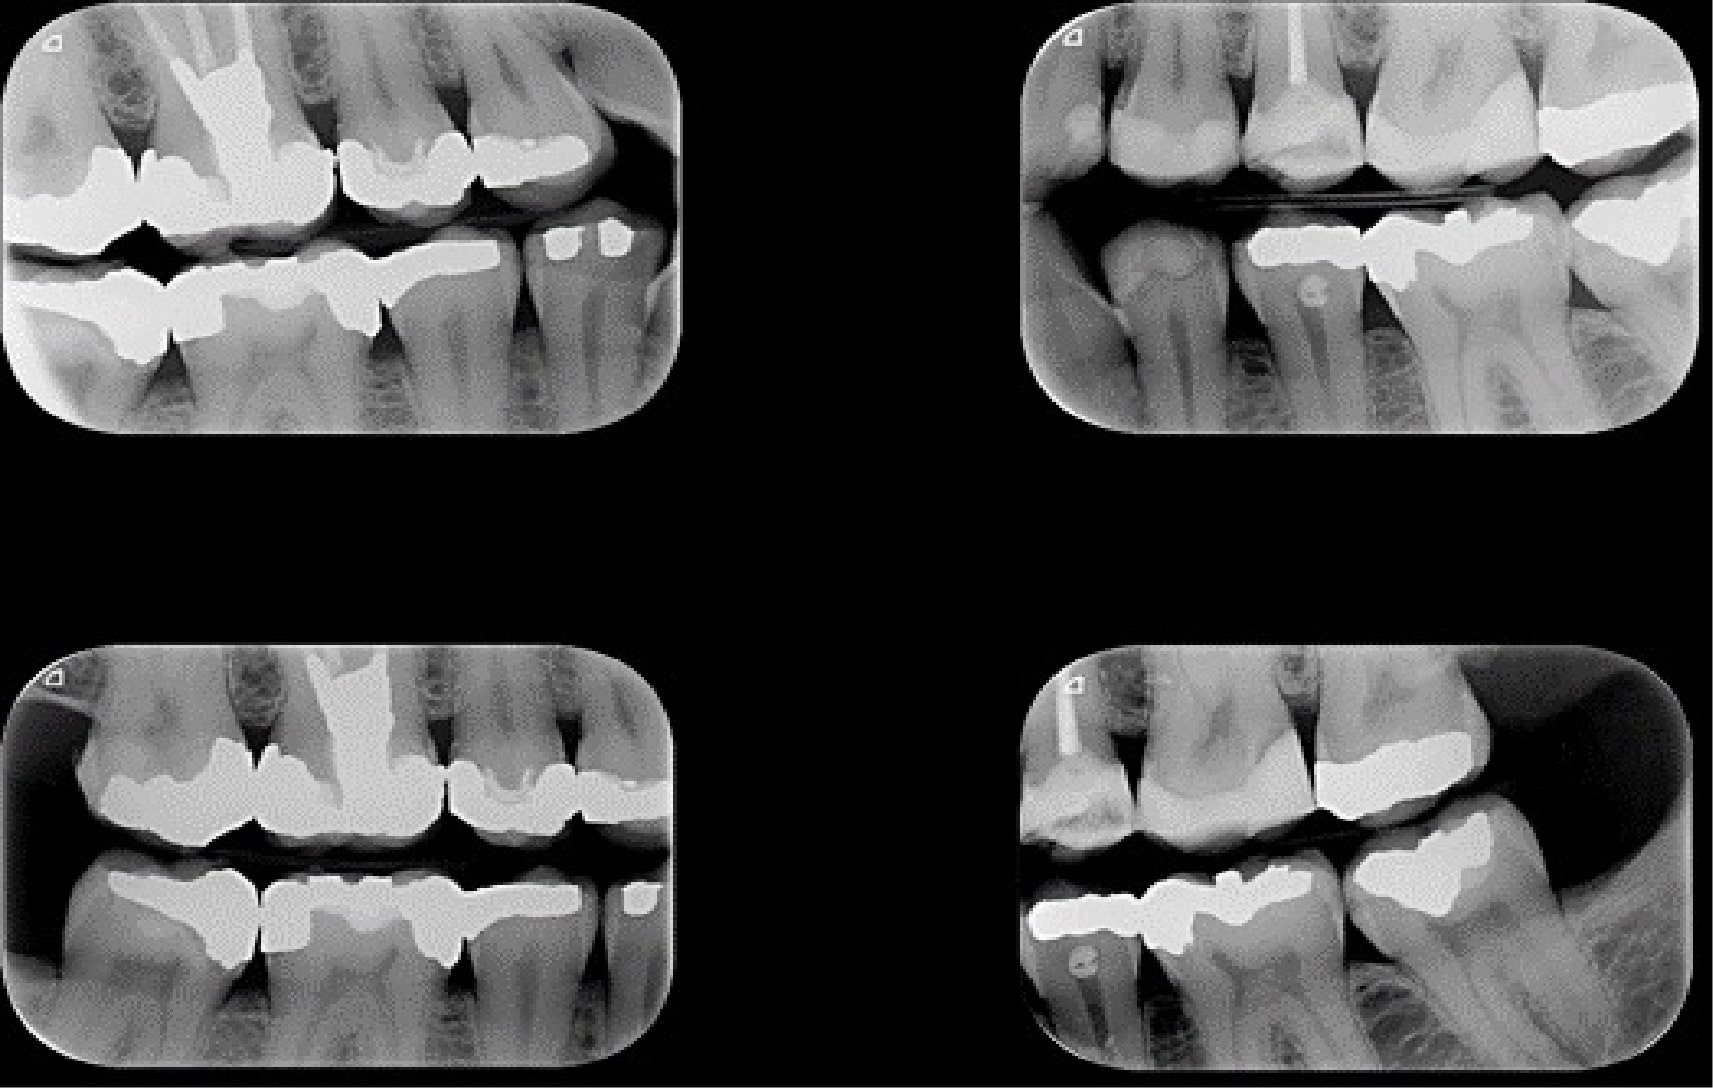

رادیوگرافی داخل دهان بایت وینگ

نوعی تصویربرداری دندانپزشکی جهت مشاهده بخشهای بین دندانی و بررسی وضعیت استخوانهای اطراف.

3. توضیح عکس بایت وینگ:

نحوه گرفتن عکس و اینکه معمولاً ۴ عکس برای دندانهای عقبی چپ و راست گرفته میشود تا وضعیت سلامت دندانها بهتر بررسی شود.4. کاربردهای رادیوگرافی بایت وینگ در دندانپزشکی:

6. تفسیر عکس بایت وینگ

تفسیر عکس بایت وینگ نیازمند به دانش و تجربه دندانپزشک بستگی دارد. دندانپزشک با بررسی تصاویر میتواند:

• پوسیدگیهای دندانی را که در مراحل اولیه قرار دارند شناسایی کند.

• وضعیت تماس بین دندانهای مجاور را بررسی کند.

• بیماریهای لثهای مانند تحلیل استخوان بین دندانی را بررسی کند.

• حضور یا عدم حضور ترمیمها و ساختارهای باقیمانده را بررسی کند.

• مشکلات مربوط به ریشه یا دیگر ساختارهای دندانی را ارزیابی کند.